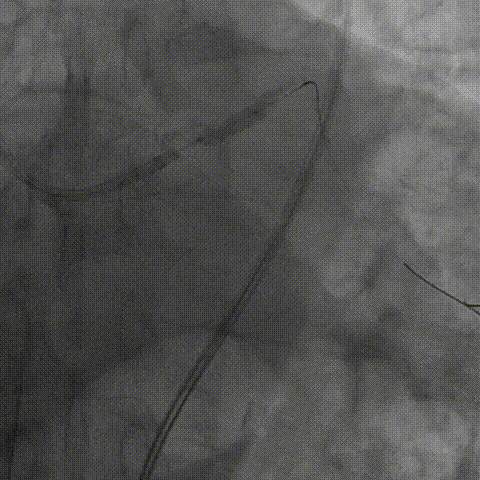

左冠造影

将EBU 3.0指引导管坐窦底,Sion导丝飘入

AO刹车导丝,2.5球囊预扩张